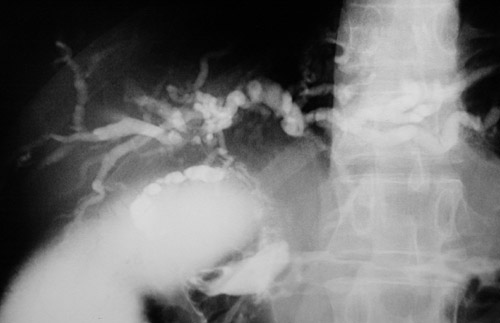

By cholangiography can be seen areas of marked segmental narrowing of the common bile duct in a case of primary sclerosing cholangitis. In this patient, there was no history of inflammatory bowel disease.